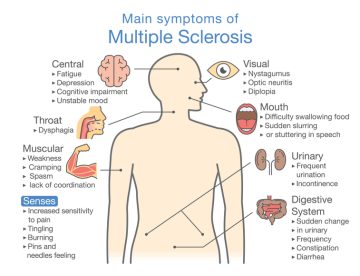

What causes Multiple Sclerosis (MS) is the damage of protective layer of myelin around some…